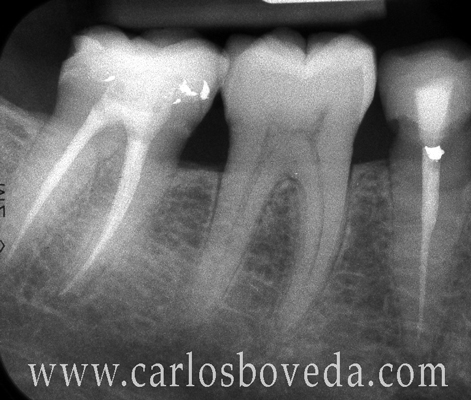

1. 10